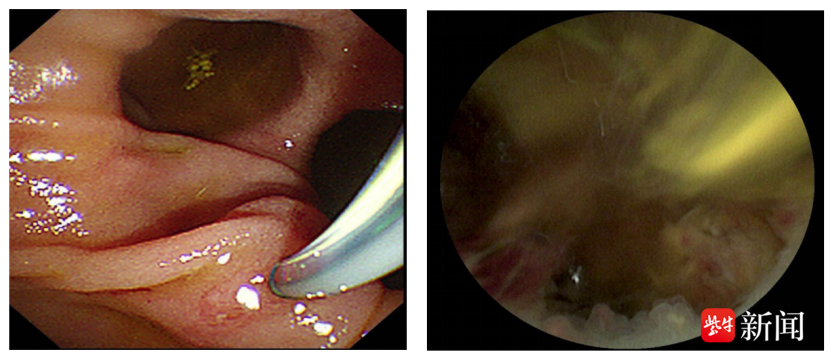

手术当天,首先由麻醉团队进行全身麻醉与监护,冯亚东主任医师团队凭借丰富的临床经验和精湛的操作技术,通过口腔这一自然腔道,将纤细的内镜精准送入胆总管。借助内镜清晰的视野,手术专家成功定位结石位置,随后用钬激光顺利将结石击碎并取出。整个手术过程仅耗时30分钟,且李爷爷体表无任何创口,最大程度降低了手术对老人身体的损伤。术后,重症医学科团队通过密切医学观察与监护,保障了术后安全过渡。经过医护人员精心照料,李爷爷的身体状况日渐好转,不仅高热、腹痛等症状消失,还能正常饮食和活动,精神状态也愈发饱满。